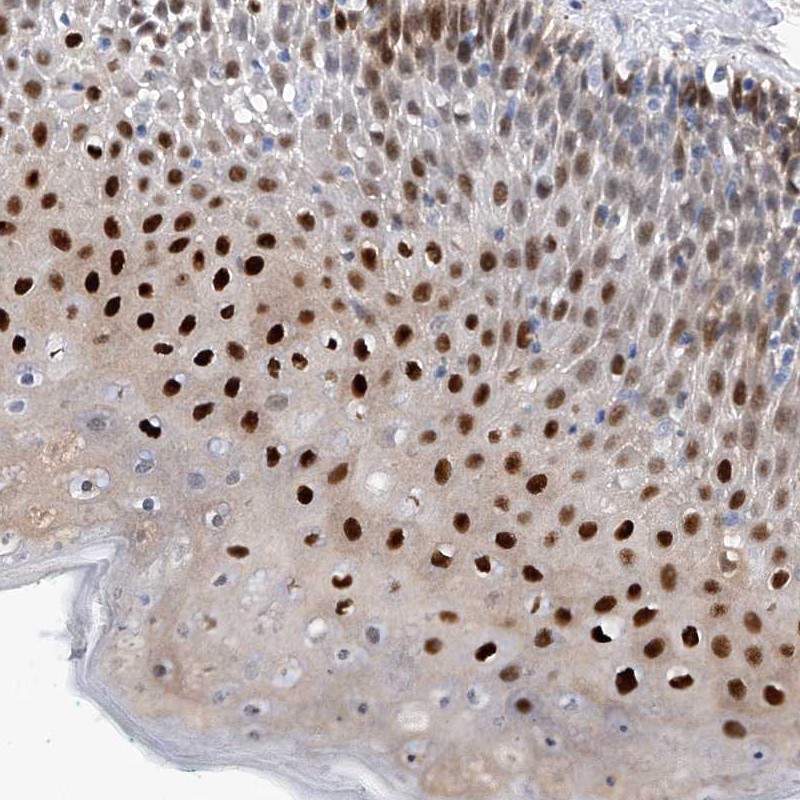

Immunohistochemical staining of human oral mucosa shows strong nuclear positivity in squamous epithelial cells.